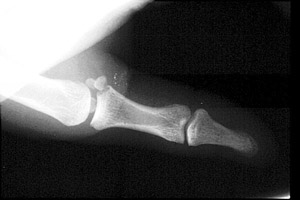

- Click on the image for a larger versionAAP radiograph of the first digit. This shows a fracture at the base of the proximal phalanx. It is intraarticular.